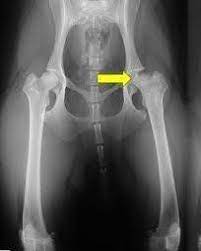

La diagnosi all’anca con studio radiografico è indicata a partire dai 4 mesi di età nelle razze già predisposte e in tutti i cani di taglia grande e gigante.

Intervento chirurgico: se il cane presenta displasia grave all’anca e dunque presenta un’articolazione compromessa si procede con l’impianto di una protesi, nel caso di un cucciolo si può intervenire con la sinfisiodesi pubica, un intervento chirurgico poco invasivo e indicato per evitare il peggiorare della patologia.

Nelle radiografie effettuate per diagnosticare un’eventuale presenza della malattia, possono emergere diversi gradi di displasia:

- Grado A – nessun segno di displasia dell’anca: la testa del femore e l’acetabolo sono congruenti tra loro, il bordo acetabolare rivolto verso la testa del femore è leggermente arrotondato, lo spazio articolare è uniforme.

- Grado B – articolazione dell’anca quasi normale: la testa del femore e l’acetabolo presentano una leggera incongruenza.

- Grado C -leggera displasia dell’anca: la testa del femore e l’acetabolo sono incongruenti e possono essere presenti delle irregolarità nella testa o collo del femore.

- Grado D – media displasia dell’anca: l’incongruenza tra testa del femore e acetabolo con presenza di sublussazione sono ben evidenti.

- Grado E – grave displasia dell’anca: lussazione o sublussazione con modificazione dell’anca di tipo displastico, deformazione della testa del femore e presenza di segni osteoartrosi.